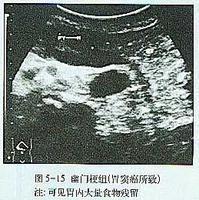

(3)超声波:胃肠超声波可见上腹或左上腹部可探及囊实性肿块,即胃型,内为无回声区,有漂浮光点及光团,随体位向重力低位移动,下胃管抽吸后,肿块亦随之缩小。